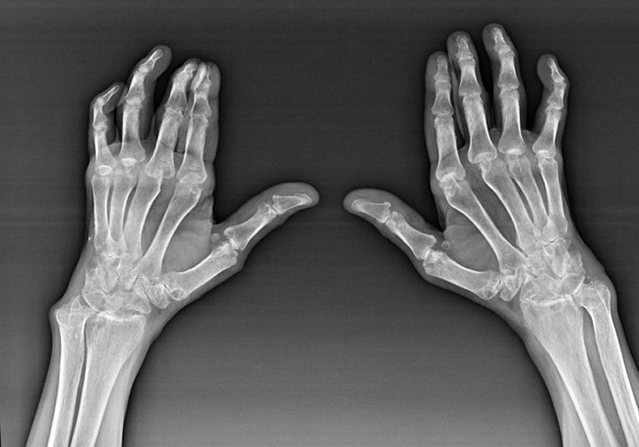

Artrite reumatoide

L'artrite reumatoide è una malattia in cui il sistema immunitario umano danneggia i tessuti del corpo. In altre parole, l'artrite reumatoide è una patologia autoimmune. Questa malattia è anche sistemica, poiché molti tessuti ne sono colpiti (muscoli, articolazioni, vasi, ecc.) e organi (Cuore, reni, polmoni, ecc.) nel corpo.

Nonostante il fatto che l'artrite reumatoide sia una malattia sistemica in misura maggiore, le articolazioni soffrono, mentre la lesione di altri tessuti e organi è sullo sfondo. Con questa malattia, possono essere influenzati quasi tutti i tipi di giunti a spazzole (pareggi da polso, pericoli carpale, articolazioni metacarpali-falange, inter-falance). La lesione è generalmente simmetrica (quelli. Le stesse giunti sono interessate) su entrambe le mani, accompagnato da gonfiore, dolore in articolazioni danneggiate. Al mattino, durante il sollevamento dal letto, c'è un po 'di rigidità nelle articolazioni interessate, che può durare circa 1 ora e poi scomparire senza traccia.

Abbastanza spesso con artrite reumatica vicino alle articolazioni interessate del pennello (Più spesso le articolazioni di piano-falange, interfalance) Appaiono noduli reumatoidi. Sono una formazione arrotondata situata sotto la pelle. Sul pennello, queste formazioni sorgono più spesso sul retro. Sulla palpazione, sono densi, inattivi, indolore. Il numero di essi può variare.